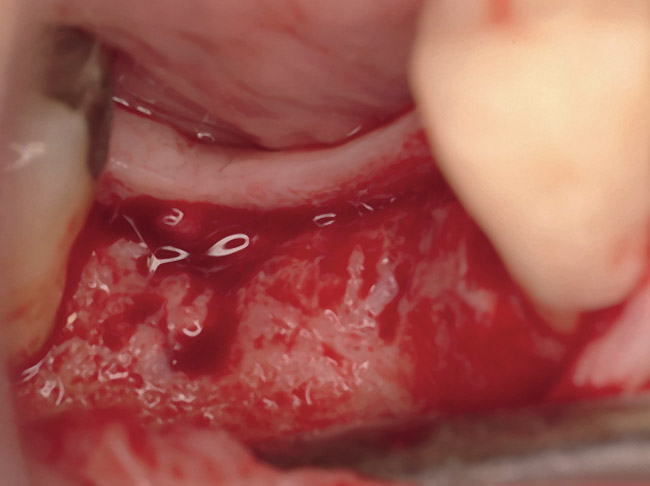

The patient was a 66-year-old man who required removal of the three mandibular right molars due to rampant caries and attachment loss. Following flap reflection and extractions, the sockets were debrided with both ultrasonic and manual instrumentation (Figure 10). The sockets of the first and second molars were augmented with rhBMP-2/ACS. The site of the third molar was obturated with a noncrosslinked, collagen plug for hemostatic purposes only.